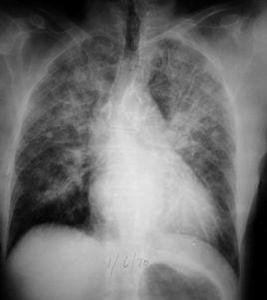

影像學檢查:

NPE早期X線及CT表現不明顯,可無異常或者僅有肺紋理增粗模糊等表現;典型X線及CT表現為雙肺彌散型肺泡浸潤,兩肺可見散在片狀陰影;晚期可表現為雙肺呈斑片狀或者雲霧狀陰影,以及典型的蝴蝶形陰影。NPE臨床症狀出現後可通過彩色超聲與心源性肺水腫加以鑑別,也可通過彩色超聲反應肺水情況。